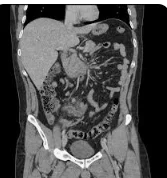

1. Imaging of Appendix By Dr. Zainab Vora

Ever found yourself wondering how to confidently identify the appendix in challenging cases? Dr. Zainab Vora has got you covered in this session, where she breaks down the imaging techniques for appendicitis and discusses its common mimics.

• Ultrasound, CT, and MRI tips for pinpointing the appendix.

• Key signs for differentiating false positives.

• Complications and how to report them accurately.